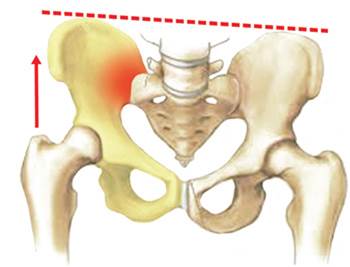

Right sacroileitis (inflammation of the sacroiliac joint) due

to leg length difference with a pelvic tilt to the left

SI joint pain (sacroileitis) is usually caused by an inflammatory response of the SI joint and can have many causes. Most sacroileitis are caused by an overload of the joint, either by excessive stiffness of the lumbar spine (e.g. after spine fusion with instrumented stabilization of the lumbar discs, etc.), by a difference in length of the legs (leading to a pelvic tilt and its overload), etc. The typical pain pattern of SI joint pain is of a pain usually located in the buttock of the affected side that may radiate from the back and/or front all the way from the thigh to the knee. Many patients describe it as a continuous pain that is exacerbated especially in postural changes, walking and in some cases even when the patient is seated.